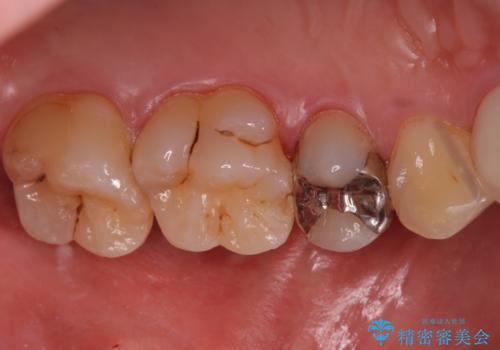

銀の詰め物を白くしたい セラミックインレーでの治療

- 銀歯が気になるためやり替えたいとのことで来院されました。

セラミックインレーで治療を行いました。

- 左上5 セラミックインレー 77,000円費用は治療当時の料金となります

口の中にチラつく銀歯は適合の良いセラミックインレーでやり替えることで綺麗にやり替えることができます。